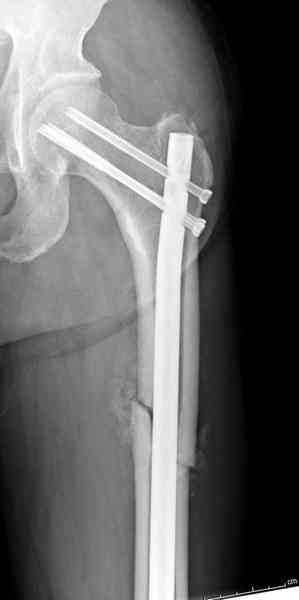

Здесь представлены снимки больного 65 лет, поступившего с диагнозом перелом

бедра после автоаварии.

В первый же день произведено антеградное штифтованием DePuy Trochanteric Nail.

На второй день (7) обнаружен пропущенный перелом,

Послеоперационные снимки